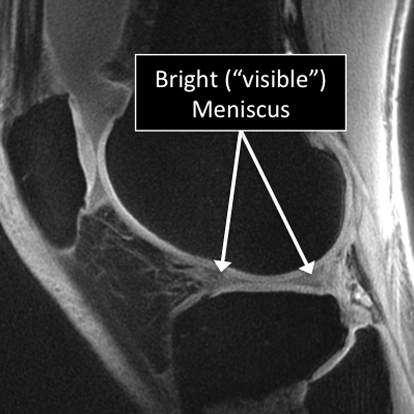

Why Translational MRI of the knee?

In the knee, as in many other parts of the body there are certain structures that can’t be seen (they look black or dark) with the standard MRI.

There are new “software” programs that allow us to see structures with different contrast (bright versus dark).

Some of these “invisible” or dark structures are unique to the knee (knee meniscus) and others are found in other parts of the body (e.g. cartilage, tendons, ligaments, cortical bone).

Knee MRI examinations using the standard MRI techniques (top) and translational MRI techniques (bottom).